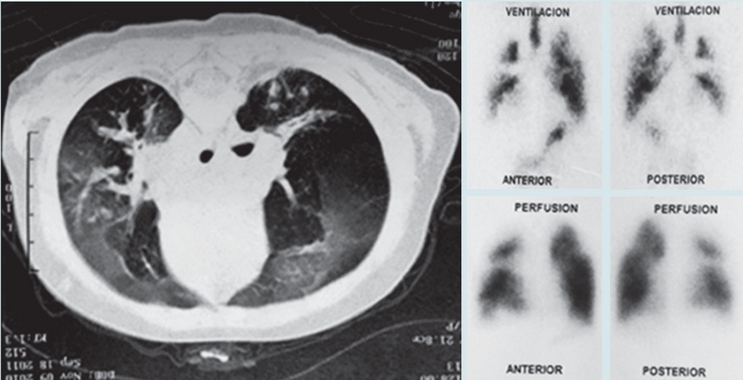

En las Figuras 1 y 2 se observan imágenes diagnósticas de algunos de nuestros pacientes y en la Figura 3 la evolución favorable de la tomografía (en un caso) después de varios años de seguimiento. En nueve casos se realizó exploración funcional respiratoria encontrando obstrucción significativa de la vía aérea en seis, obstrucción leve en dos y ausencia de obstrucción en uno; en 3/8 pacientes se observó reversibilidad del volumen espiratorio forzado en el primer segundo (VEF1). Se hizo seguimiento de la función pulmonar en cuatro pacientes observándose deterioro de la misma en tres (Figura 4). En cuanto a la presión pulmonar se encontró inicialmente elevada en el 43% de los casos, observándose en su seguimiento, disminución en cinco y aumento en uno.

Figura 1 Caso 6: Radiografía de tórax con importante atrapamiento de aire y tomografía con patrón en mosaico y bronquiectasias, hallazgos característicos de la bronquiolitis obliterante post-infecciosa.